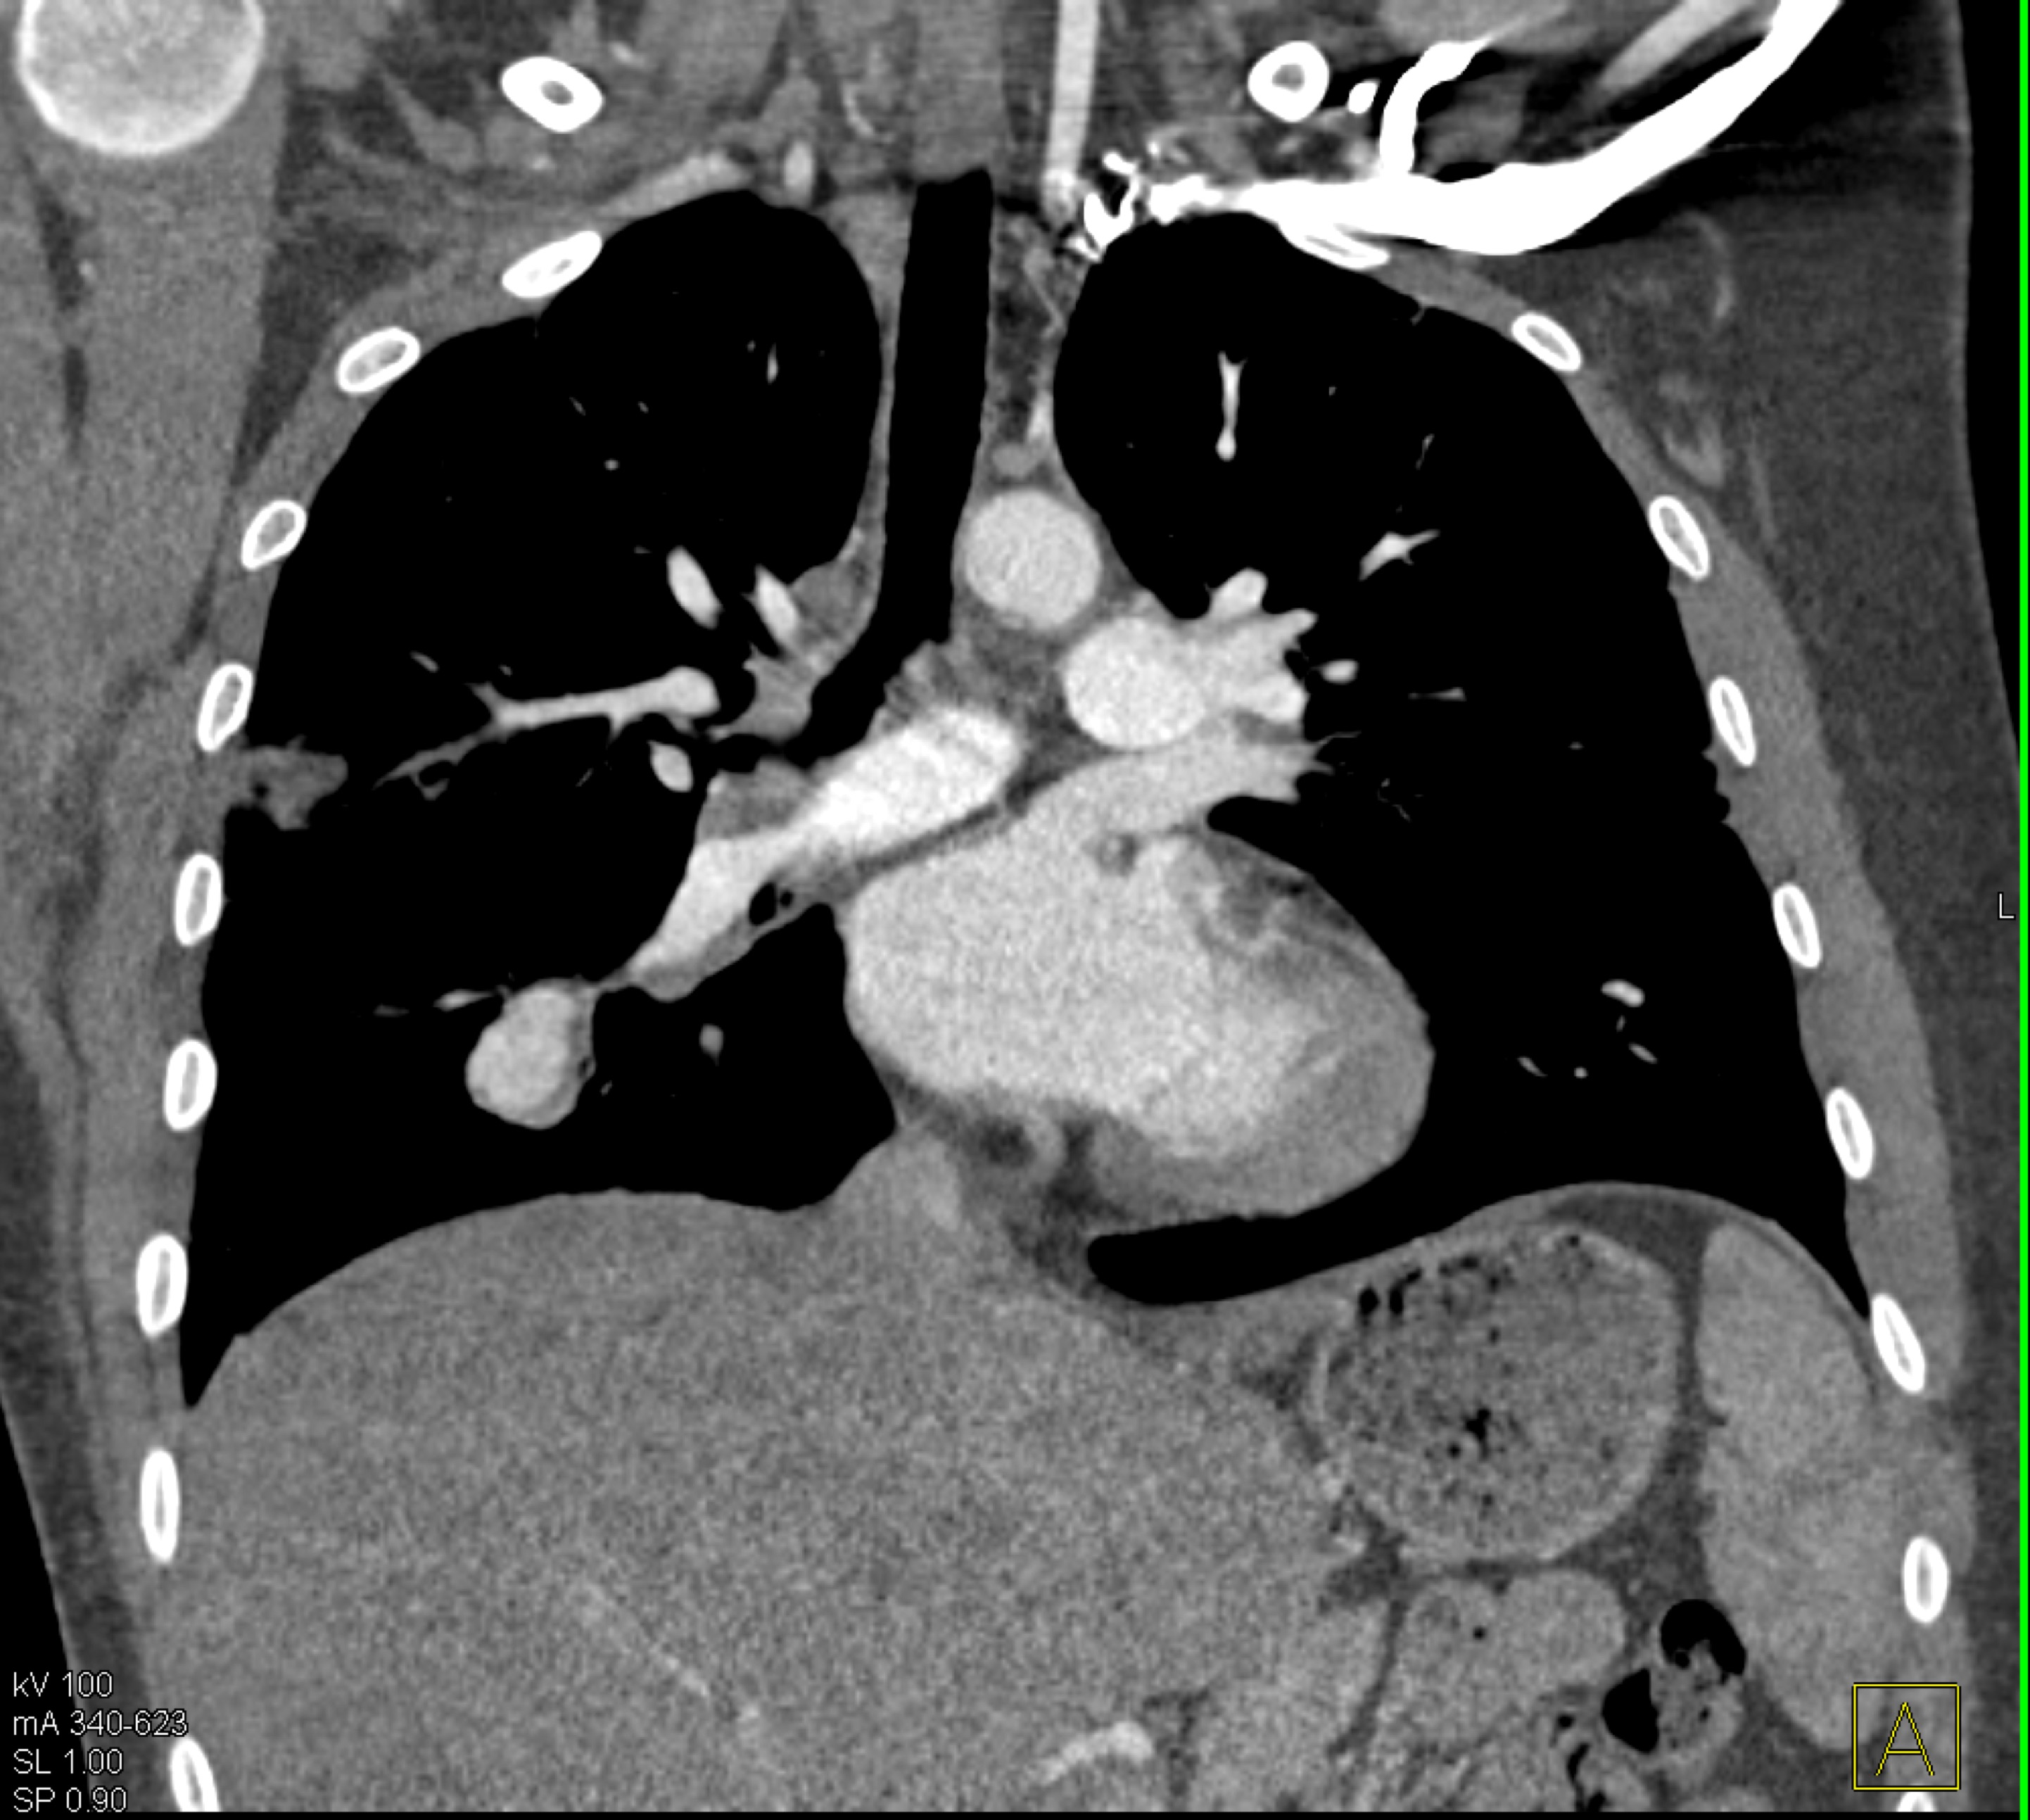

3) The most likely diagnosis in this case is?

lung cancer

lymphoma

pulmonary artery aneurysm

sarcoidosis